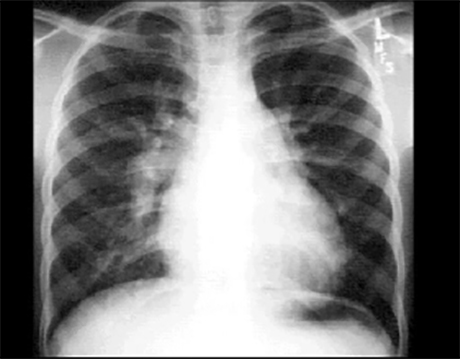

PA

These chest X rays show right ventricular enlargement, a dilated pulmonary trunk and increased pulmonary vascularity. In this PA view, right ventricular enlargement is suggested by the minimally elevated cardiothoracic ratio and the presence of an upturned apex. The dilated pulmonary trunk is manifested by the convex density below the aortic knob. There is also prominence of the pulmonary arteries, particularly well seen as dilatation of the right pulmonary artery. Such dilatation is compatible with increased blood flow, as seen with left-to-right shunts.